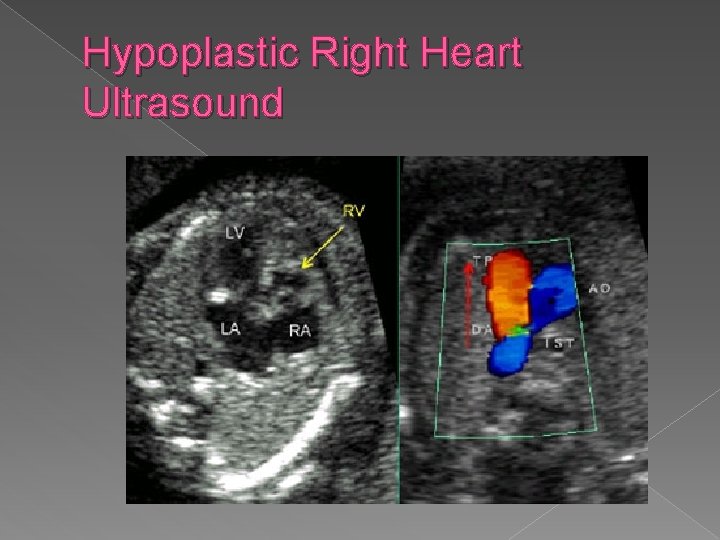

Hypoplastic Right Heart Syndrome � Generally occurs secondary to pulmonary atresia, with an intact interventricular septum. � Sonographic findings: � Absent or markedly small right ventricle on 4 chamber view � Absent or small pulmonary artery

Hypoplastic right heart syndrome › Absent or markedly small right ventricle on 4 chamber view › Absent or small pulmonary trunk

Hypoplastic Right Heart Ultrasound